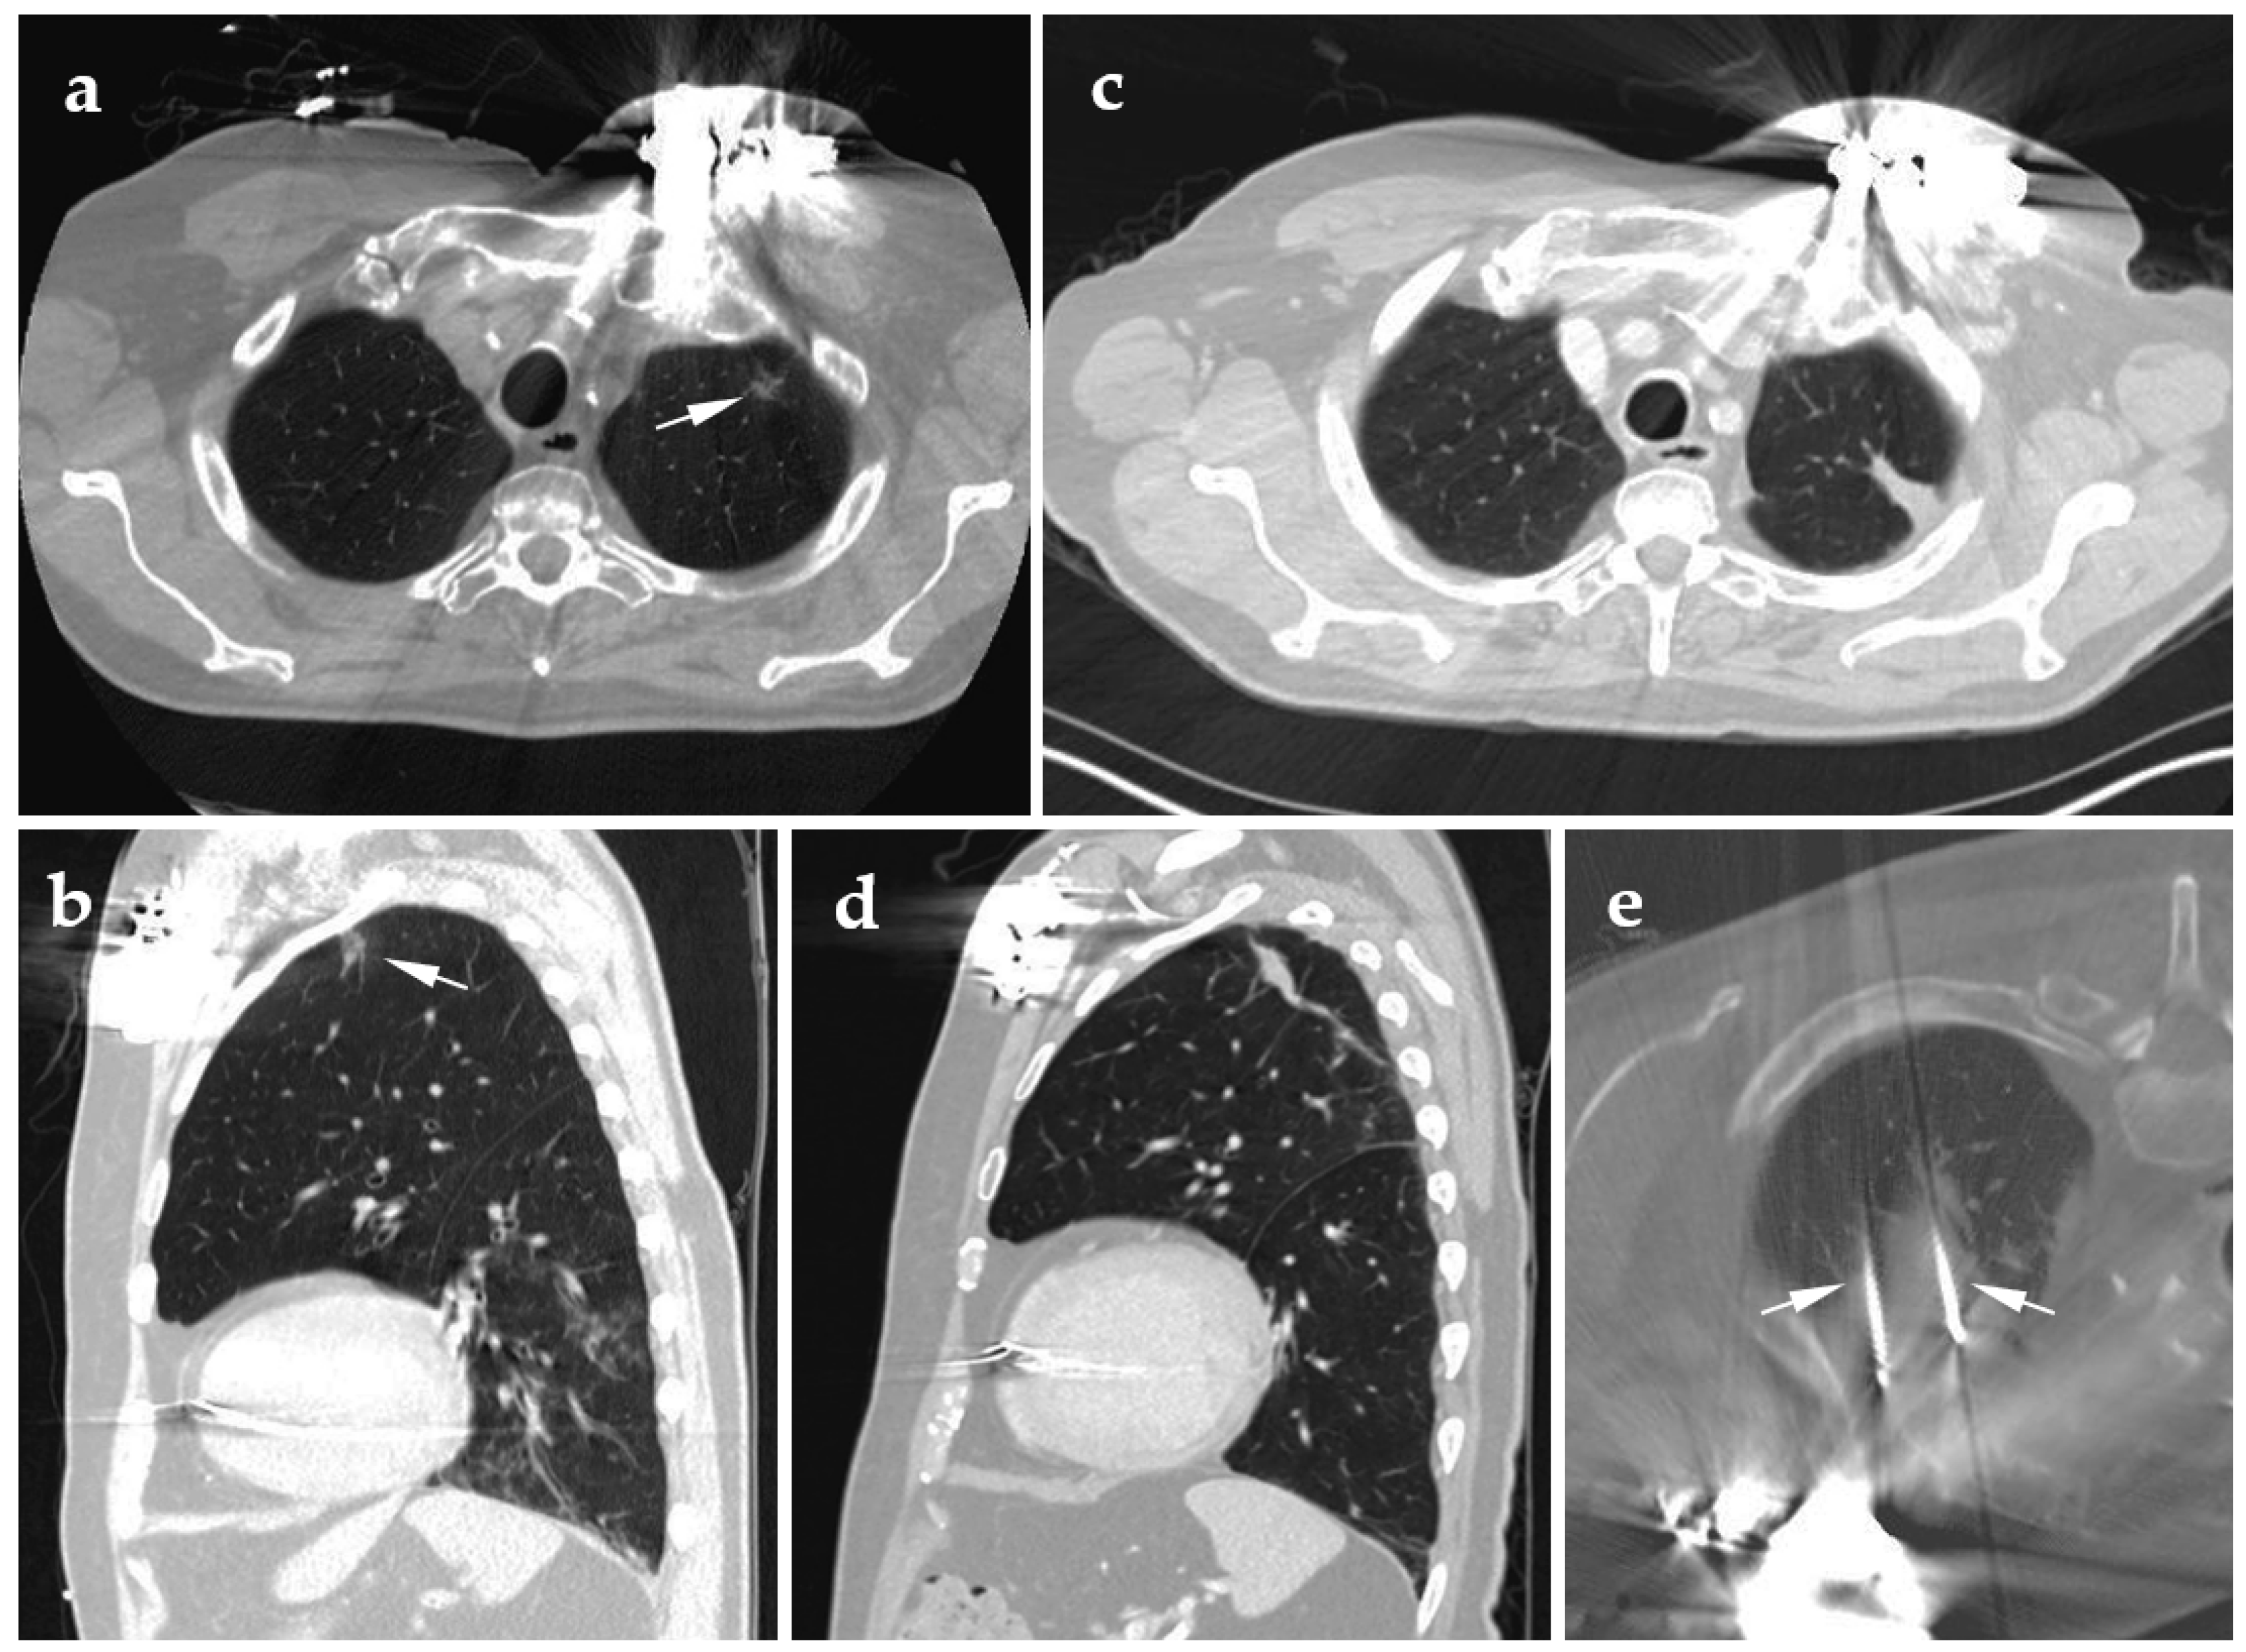

4.1. Cryoablation